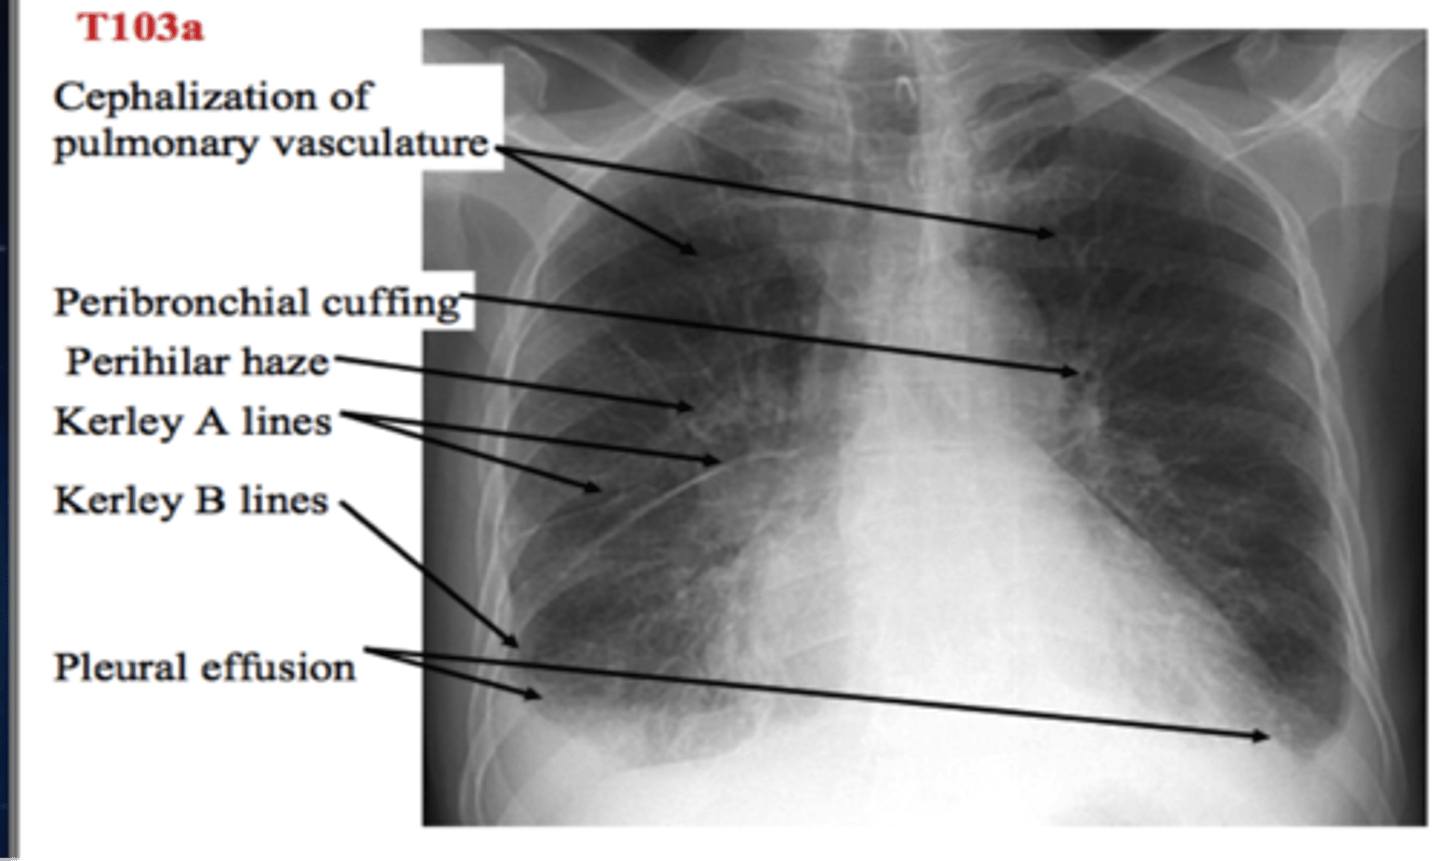

seen in pulmonary edema

Kerley B lines

-fluid accumulates and the bronchial waller becomes thicker and appearance ring like

Peribronchial cuffing on XR

-kerley lines

-pleural effusion

-peribronchial cuffing

-hydrostatic intersitital edema

CHF on a chest XR

-b/l perihilar airspace disease with diffuse interstitial markings

-kerley B lines

(PICTURE ON LEFT)

Pulmonary edema appearance